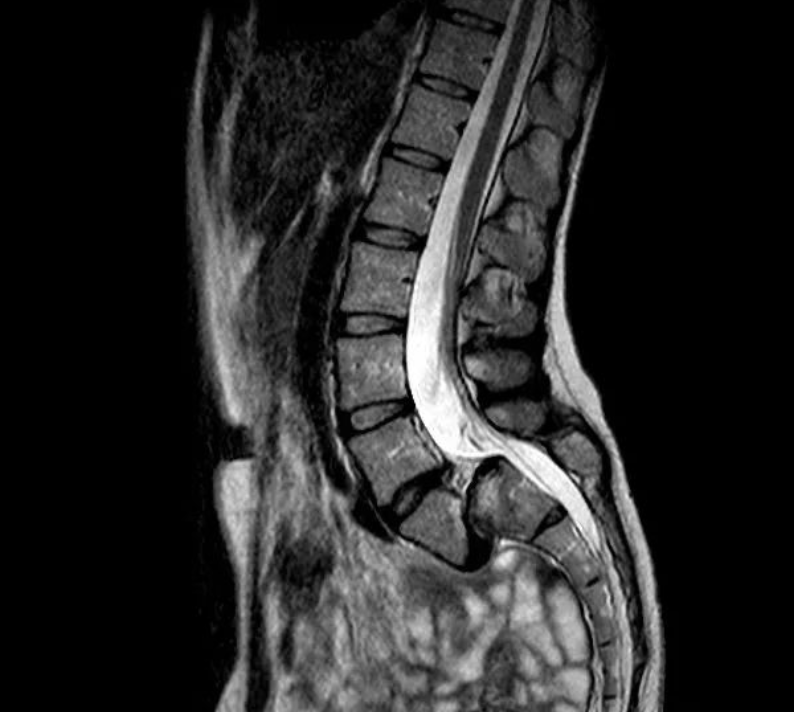

核磁共振检查(MRI)

核磁共振检查(MRI)可观察腰椎神经根受压情况及各椎间盘退变程度,有助于确定减压和融合范围。

椎弓峡部崩裂面粗糙的低信号带

双关节征、双边征和椎间盘夹心征